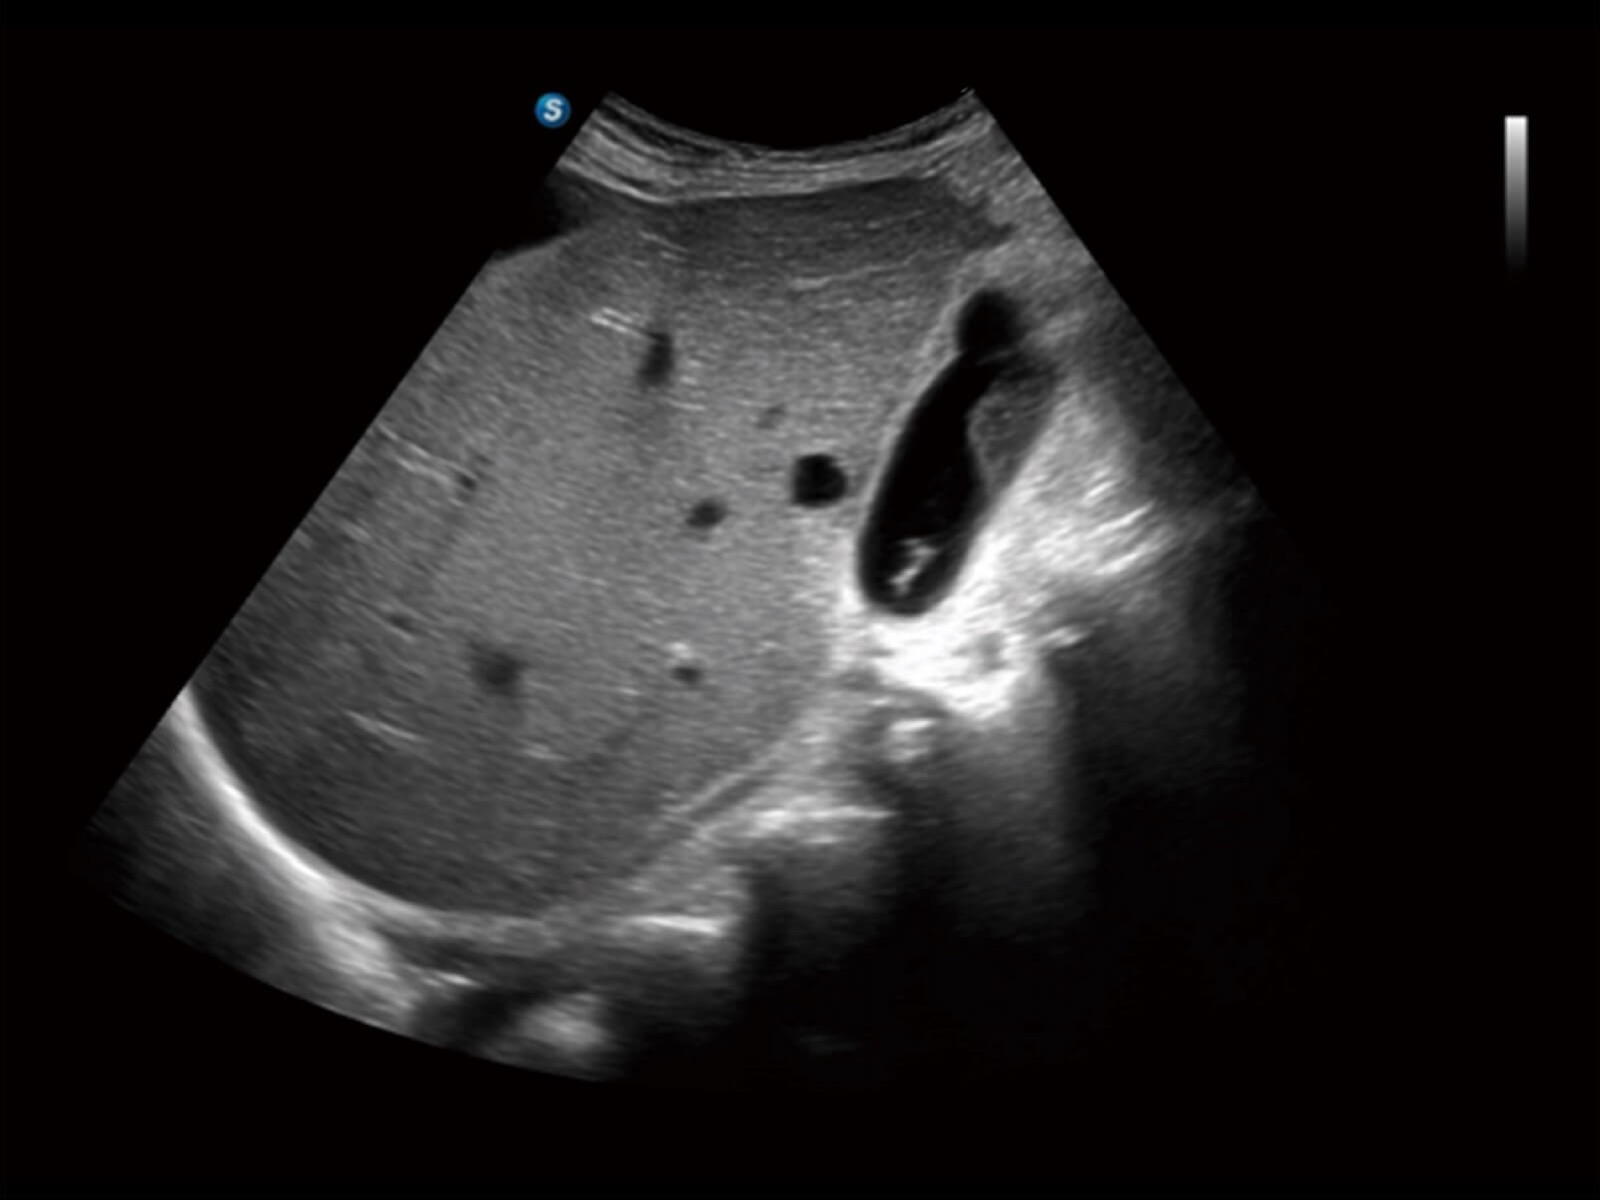

X10作为一款多功能便携式超声产品,其解决方案融合尖端技术与临床需求,能支持各类场景下的高效检查流程,助力医疗专业人员在基础医疗场景中作出更有把握的诊断。

全身应用

妇产应用

专科应用